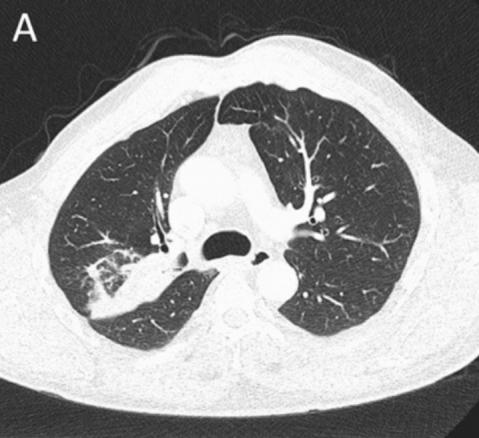

图1 胸部CT

CT检查示右后上叶实变,没有看到含气支气管影,怀疑是支气管内肿瘤导致阻塞后实变(图1 A)。支气管内膜异常也出现在中间支气管和左主支气管(图1B、1C)。支气管镜检查显示,左侧主支气管、右侧中间支气管和右上叶后段支气管有大量息肉样肿块。(图2)